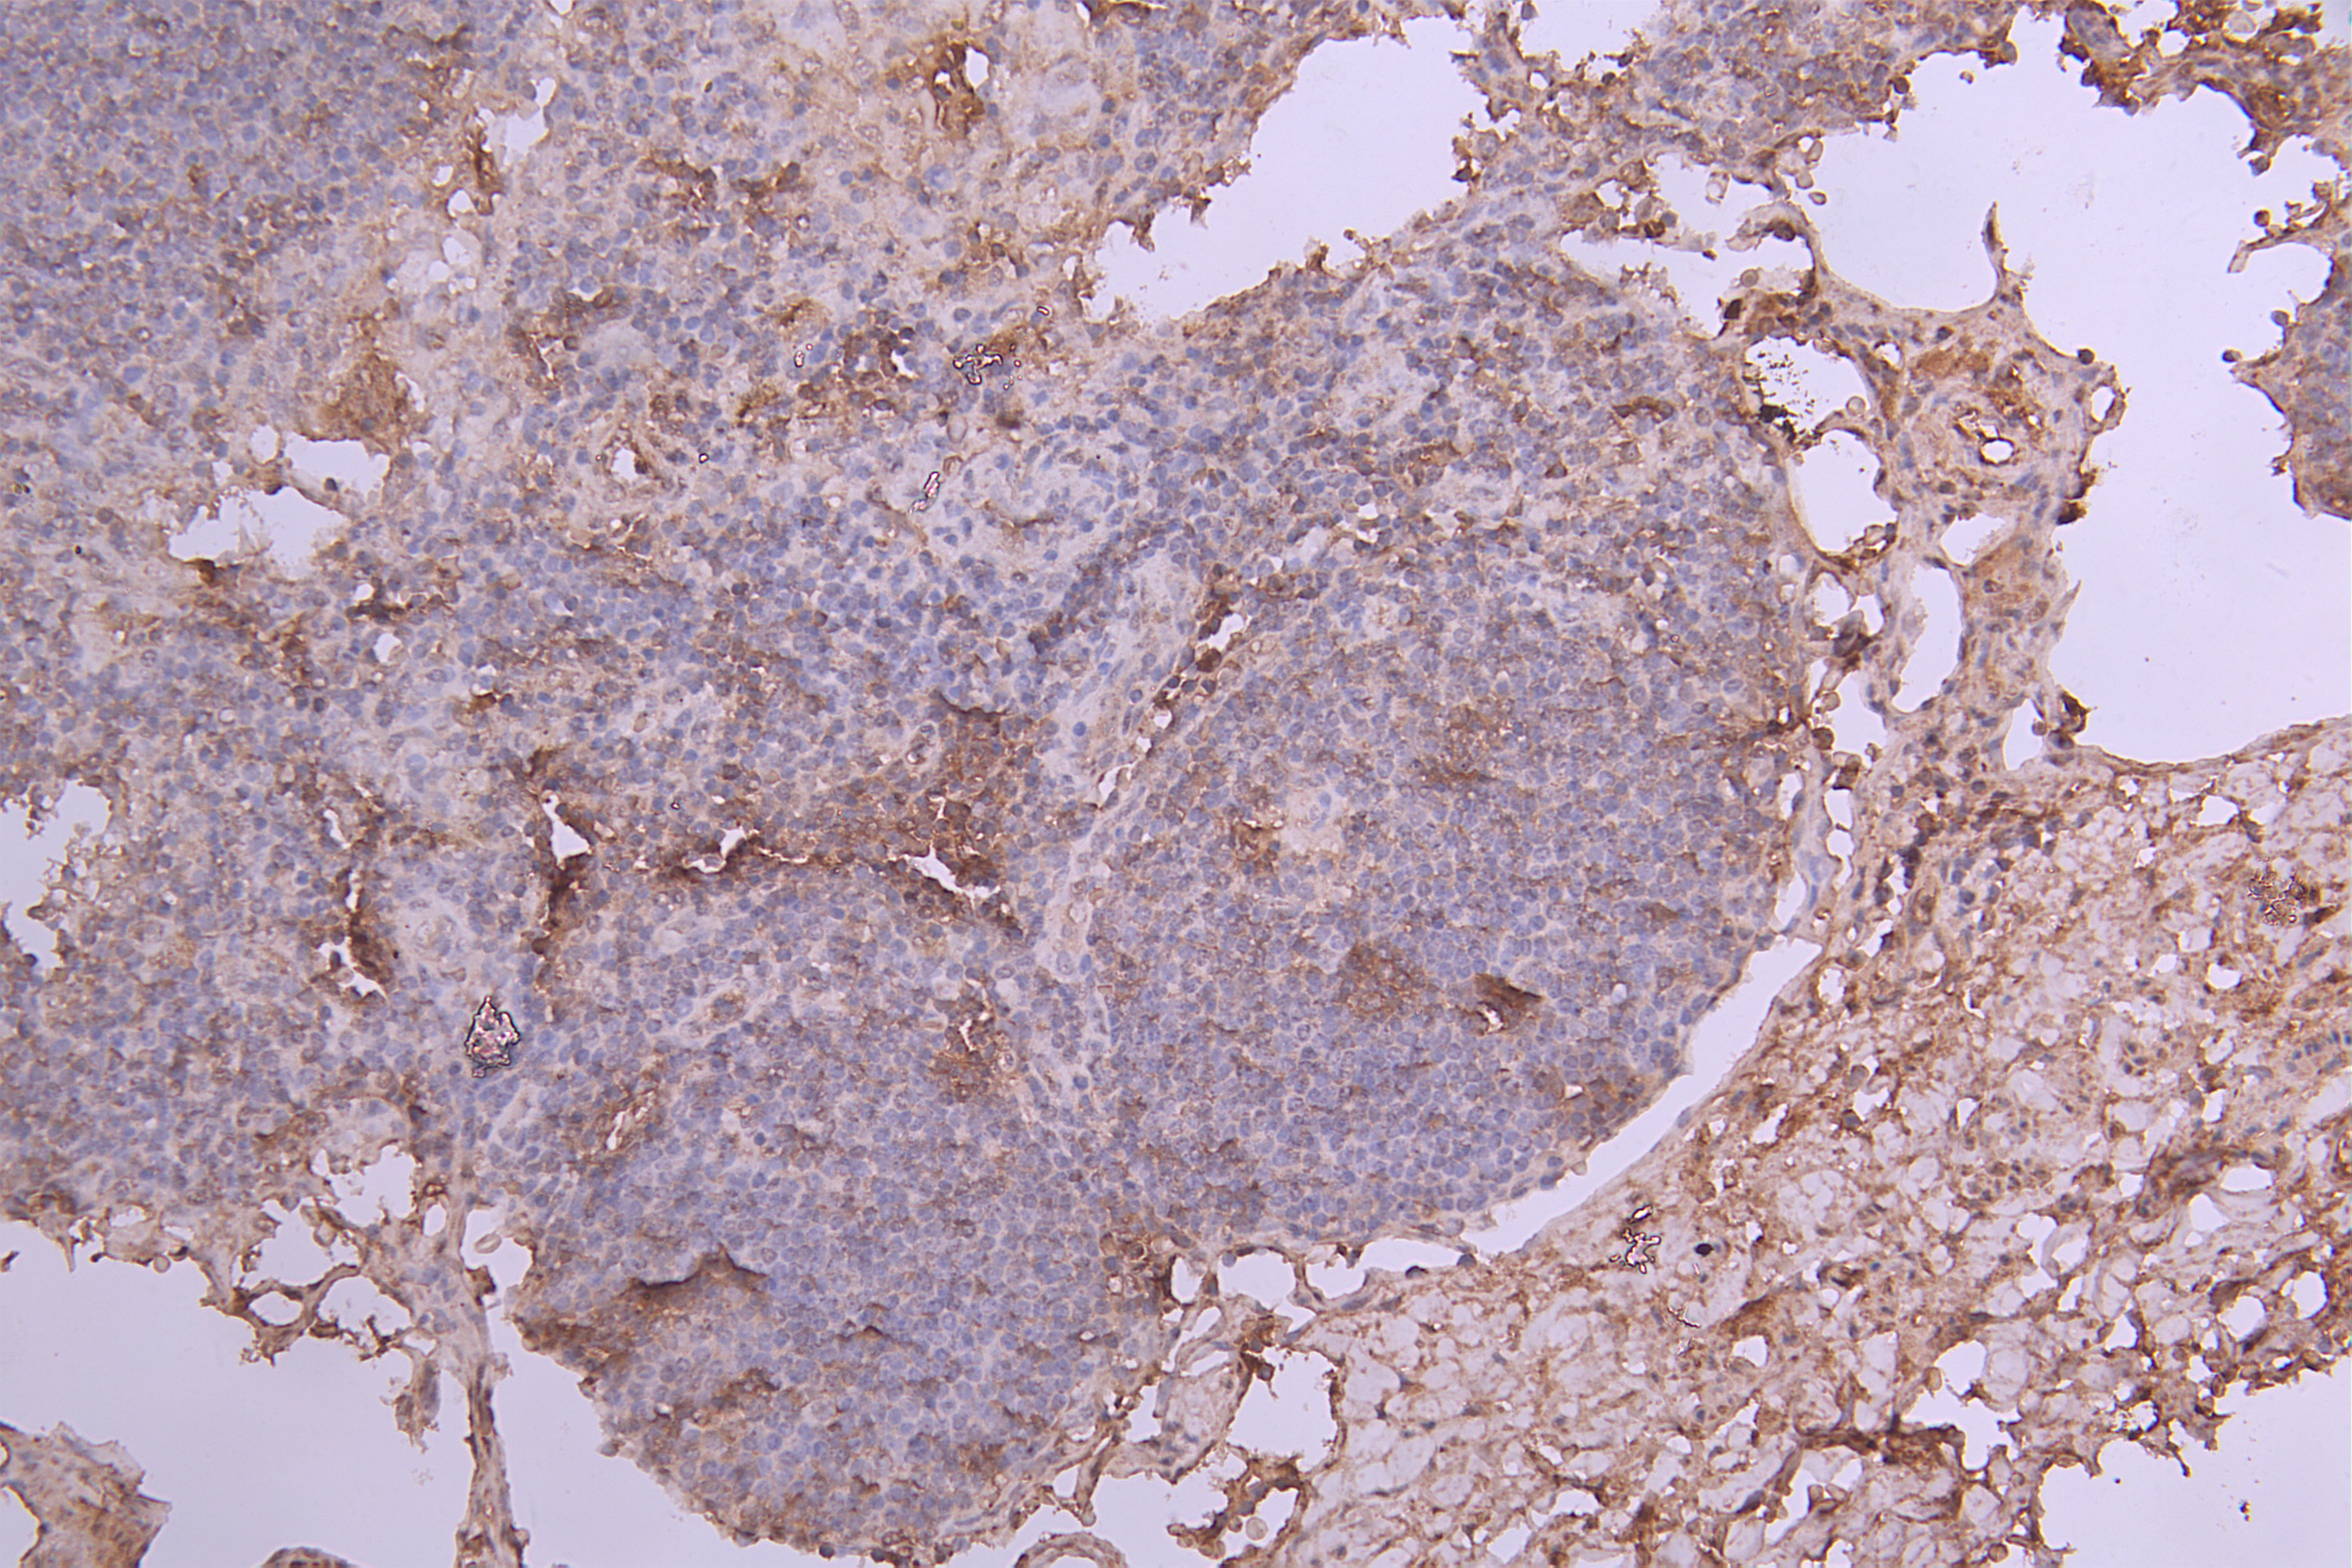

IHC image of CSB-RA011664MA2HU diluted at 1:100 and staining in paraffin-embedded human lymph node tissue performed on a Leica BondTM system. After dewaxing and hydration, antigen retrieval was mediated by high pressure in a citrate buffer (pH 6.0). Section was blocked with 10% normal goat serum 30min at RT. Then primary antibody (1% BSA) was incubated at 4°C overnight. The primary is detected by a Goat anti-Human IgG labeled by HRP and visualized using 0.05% DAB.

產品描述:CSB-RA011664MA2HU IL6重組單克隆抗體是針對白細胞介素6(Interleukin-6)靶點開發的高特異性科研試劑。IL-6作為多效性細胞因子,在免疫應答、炎癥反應及腫瘤發生中發揮關鍵調控作用,其異常表達與類風濕性關節炎、細胞因子風暴及多種惡性腫瘤密切相關。本產品采用重組單克隆抗體技術制備,經嚴格驗證適用于酶聯免疫吸附測定(ELISA)和免疫組織化學(IHC)實驗,在IHC應用中針對石蠟包埋組織切片展現出優異的抗原識別能力,推薦使用稀釋比例為1:50至1:200,實驗數據顯示其具備良好的信號強度和背景潔凈度。該抗體適用于探索炎癥相關疾病的分子機制、分析腫瘤微環境中細胞因子的空間分布特征,以及評估疾病模型中的IL-6表達水平,為免疫調控研究、藥物靶點篩選和病理機制解析提供可靠工具。所有批次產品均經過嚴格質控,確保實驗結果的穩定性和可重復性。

Application Recommended Dilution IHC 1:50-1:200 -